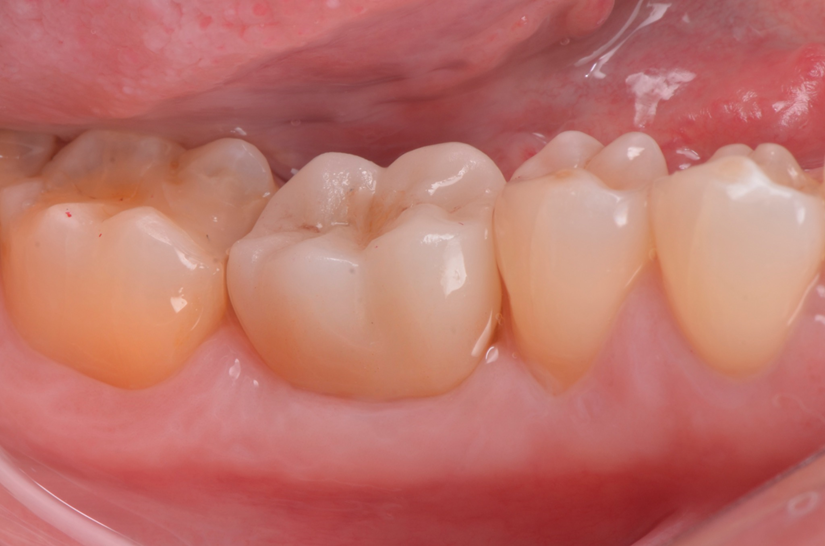

Escaneamento digital e reabilitação com coroa definitiva

Neste caso, a sobreposição digital entre o cicatrizador escaneado e o desenho da coroa possibilitou comparar perfis de emergência com excelente adaptação clínica, contribuindo para um resultado estético e funcional adequado.

A associação entre cirurgia guiada, biomateriais osteocondutores, componentes personalizados e fluxo digital completo permitiu uma reabilitação precisa, estética e minimamente invasiva do dente 46. O uso do cicatrizador impresso personalizado mostrou-se eficaz na preservação do perfil de emergência, otimizando a integração entre cirurgia e prótese. Essa abordagem representa uma tendência moderna na Implantodontia digital, com benefícios clínicos e biológicos evidentes para o paciente.